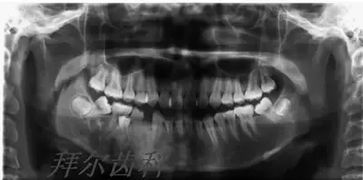

拔牙后注意事項